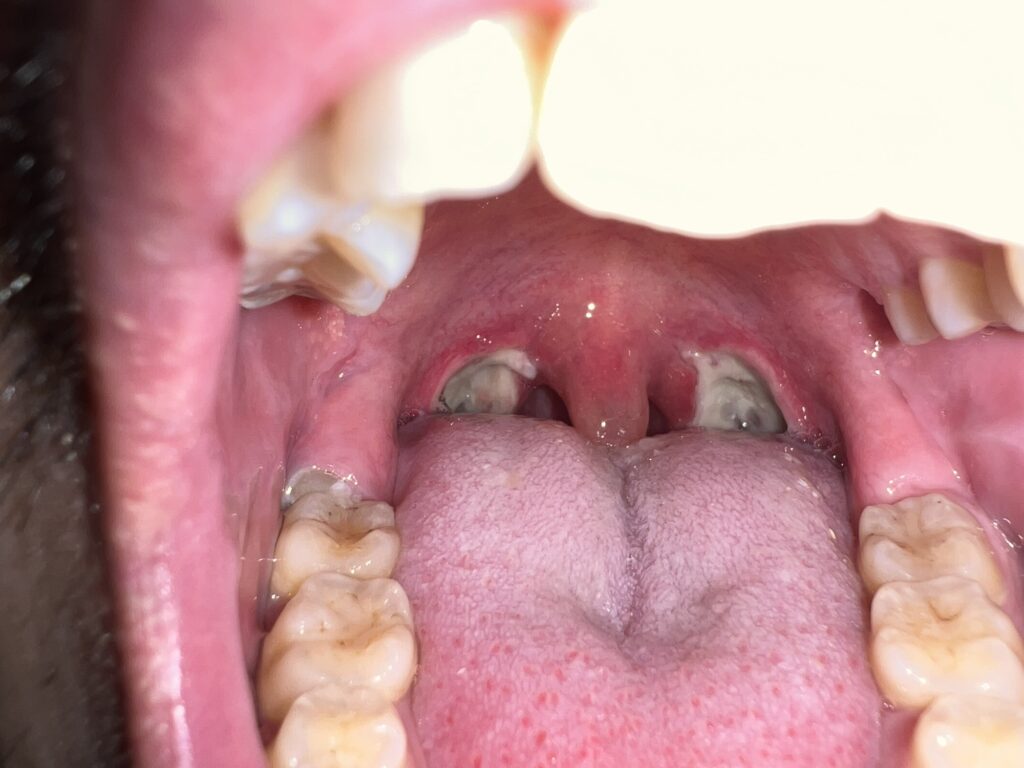

11月20日

手術箇所がどんどん白くなってカサブタが多くなって来てますねぇ